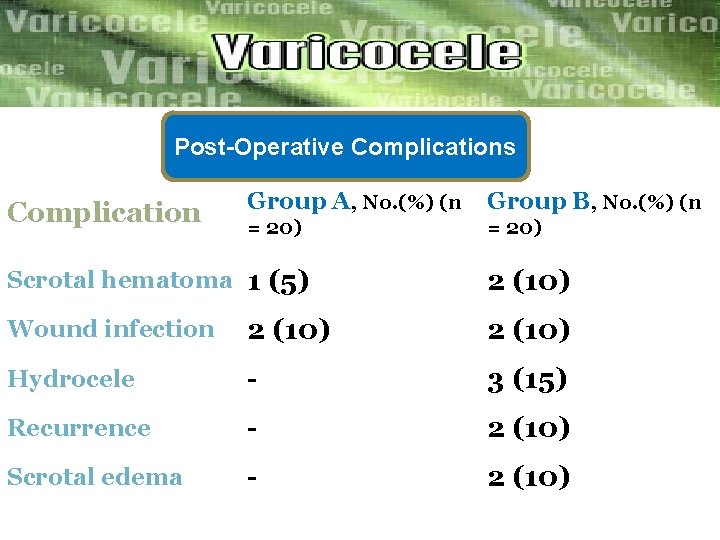

Post-Operative Complications Complication Group A, No. (%) (n Group B, No. (%) (n = 20) Scrotal hematoma 1 (5) 2 (10) Wound infection 2 (10) Hydrocele - 3 (15) Recurrence - 2 (10) Scrotal edema - 2 (10)